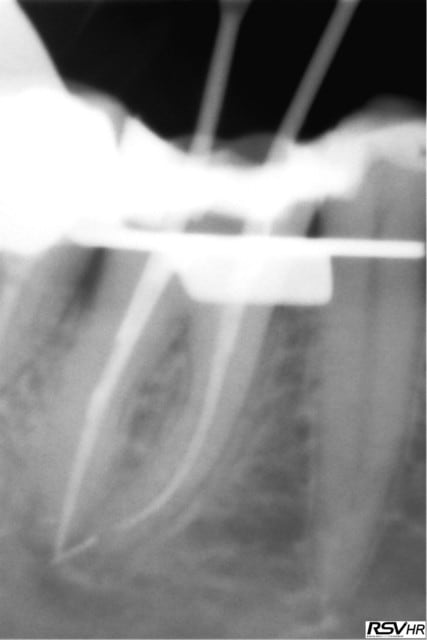

Autrement j'ai joint 2 radios en 2011 ou suite à une bio sous digue+ hypo à 2,5% j'ai cassé 2 Niti un ,racine mésiale de 46

et en distal dans sans doute un canal secondaire.Tout cela baignait dans l'hypo.Je n'étais pas fière( surement pas assez de cathétérisme apex mésial dépassé etc...)Et donc j'ai fait un suivi

et en 2013 le périapex semble guéri,pas de sensibilité à la pression, la nature est sympa et bien sur je ne casse plus de Niti

dans mes endos.....

2011 yf6dsf - Eugenol

2013 dibdsa - Eugenol